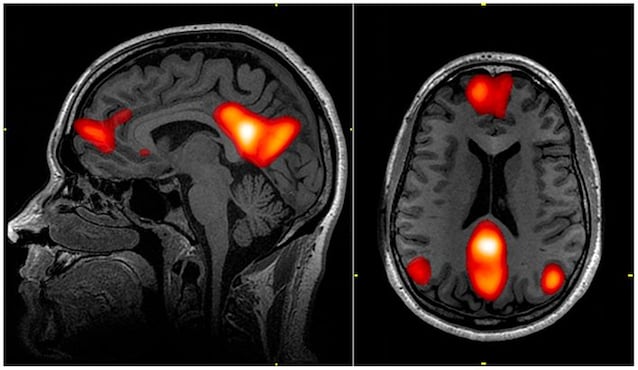

Hypnose er en Endret bevissthetstilstand der hjernen oppfører seg på en bestemt måte. For eksempel noen områder involvert i Kritisk skjønn og som svar på miljøstimuleringensom Front Trap Cortexer mindre aktive. Dette fører til en tilstand av Ultra -fokusert oppmerksomhet og til en større antydelighet. Samtidig er aktiviteten til Standard modusnettverk – en aktiv hjernekrets når Vi reflekterer over oss selv – dermed favorisere en følelse av port.